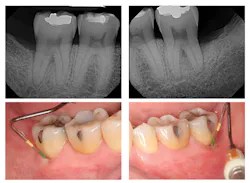

Figure 2: Six-month post-treatment radiographs and photos

Evaluation-A six-month evaluation demonstrated reattachment (see Figure 2). The radiograph of tooth No. 18 exhibited 7.4 mm bone loss on the distal surface, reflecting an increased bone height of 4.4 mm. For tooth No. 31, the radiograph exhibited 6.2 mm bone loss, reflecting an increased bone height of 2.2 mm. Epithelial attachment gain was clinically evident as well (see Table 2). Pocket depths had marked improvement with elimination of furcation involvement on both teeth, decreased mobility of tooth No. 18, and no increase in recession. The patient also submitted three-year post-treatment radiographs taken by the dental hygienist of record (see Figure 3) with evidence of bone stability.